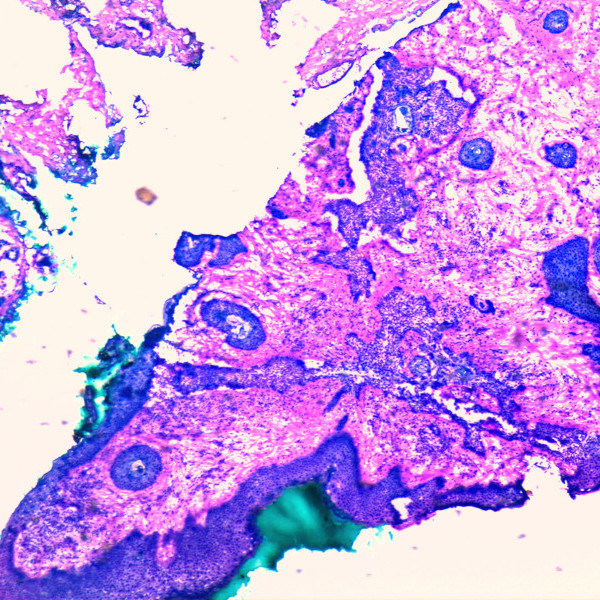

In the frozen section procedure, 100% of the surgical margins of the specimen are examined under a microscope by a dermatosurgeon and, if necessary, additionally confirmed by a pathologist, depending on the legal situation in the respective country. If the tumor has not yet been completely excised, in a next stage little more tissue is removed until all the margins are 100% tumor free.